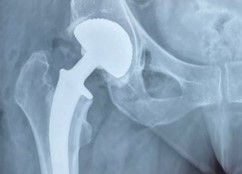

La Chirurgie Orthopédique est assurée par une équipe de quatre praticiens spécialisés en chirurgie du membre supérieur et en chirurgie du membre inférieur. La Clinique dispose d'un équipement médical de pointe pour assurer des diagnostics précis et des traitements efficaces. Notre équipe réalise des interventions chirurgicales pour les blessures, les fractures et les troubles orthopédiques, y compris la chirurgie arthroscopique et la chirurgie de prothèse articulaire.